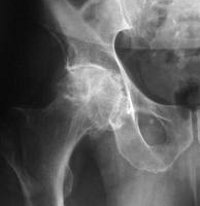

Рентгенография тазобедренного сустава

Рентгенография тазобедренного сустава. Рентгенологическое исследование проводится с целью оценки состояния вертлужной впадины подвздошной кишки, головы, шеи и наклона бедра. В травматологии его применяют в случаях подозрения на перелом головки и шейки бедра, поперечный и межточечный перелом, отделение большого вертела или вывих бедра, а также при остеомиелите. В других областях медицины его используют в процессе диагностики воспалительных и дегенеративно-дистрофических заболеваний, врожденных аномалий, первичных и метастатических опухолей этого места. Процедура не требует специальной подготовки, ее можно проводить как в стационарных, так и в амбулаторных условиях.

Наиболее распространенным показанием для рентгенографии тазобедренного сустава при травме является подозрение на перелом бедра (обычно у пожилых пациентов). Реже назначают исследование при подозрении на вывих бедра, разрыв большого вертела, межточечный или поперечный перелом. Кроме того, рентгенологическое исследование этой области в травматологии представлено при остеомиелите проксимального отдела бедренной кости. В ортопедии методика применяется при остеоартрозе, остеопорозе, асептическом некрозе, кистозной перестройке и нарушениях развития (дисплазия). В гнойной хирургии процедура проводится при гнойном артрите, онкологии, при первичных или метастатических опухолях, при ревматологии, при ревматологических заболеваниях с поражением тазобедренного сустава.